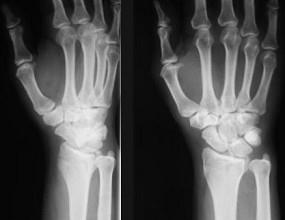

问题 男,22岁,滑冰时摔倒右手撑地时受伤,请结合CR片,选出最可能的诊断 ( )

选项 A、桡骨远端骨折 B、反柯莱斯骨折 C、蒙泰贾骨折 D、加莱阿齐骨折 E、柯莱斯骨折

答案 A